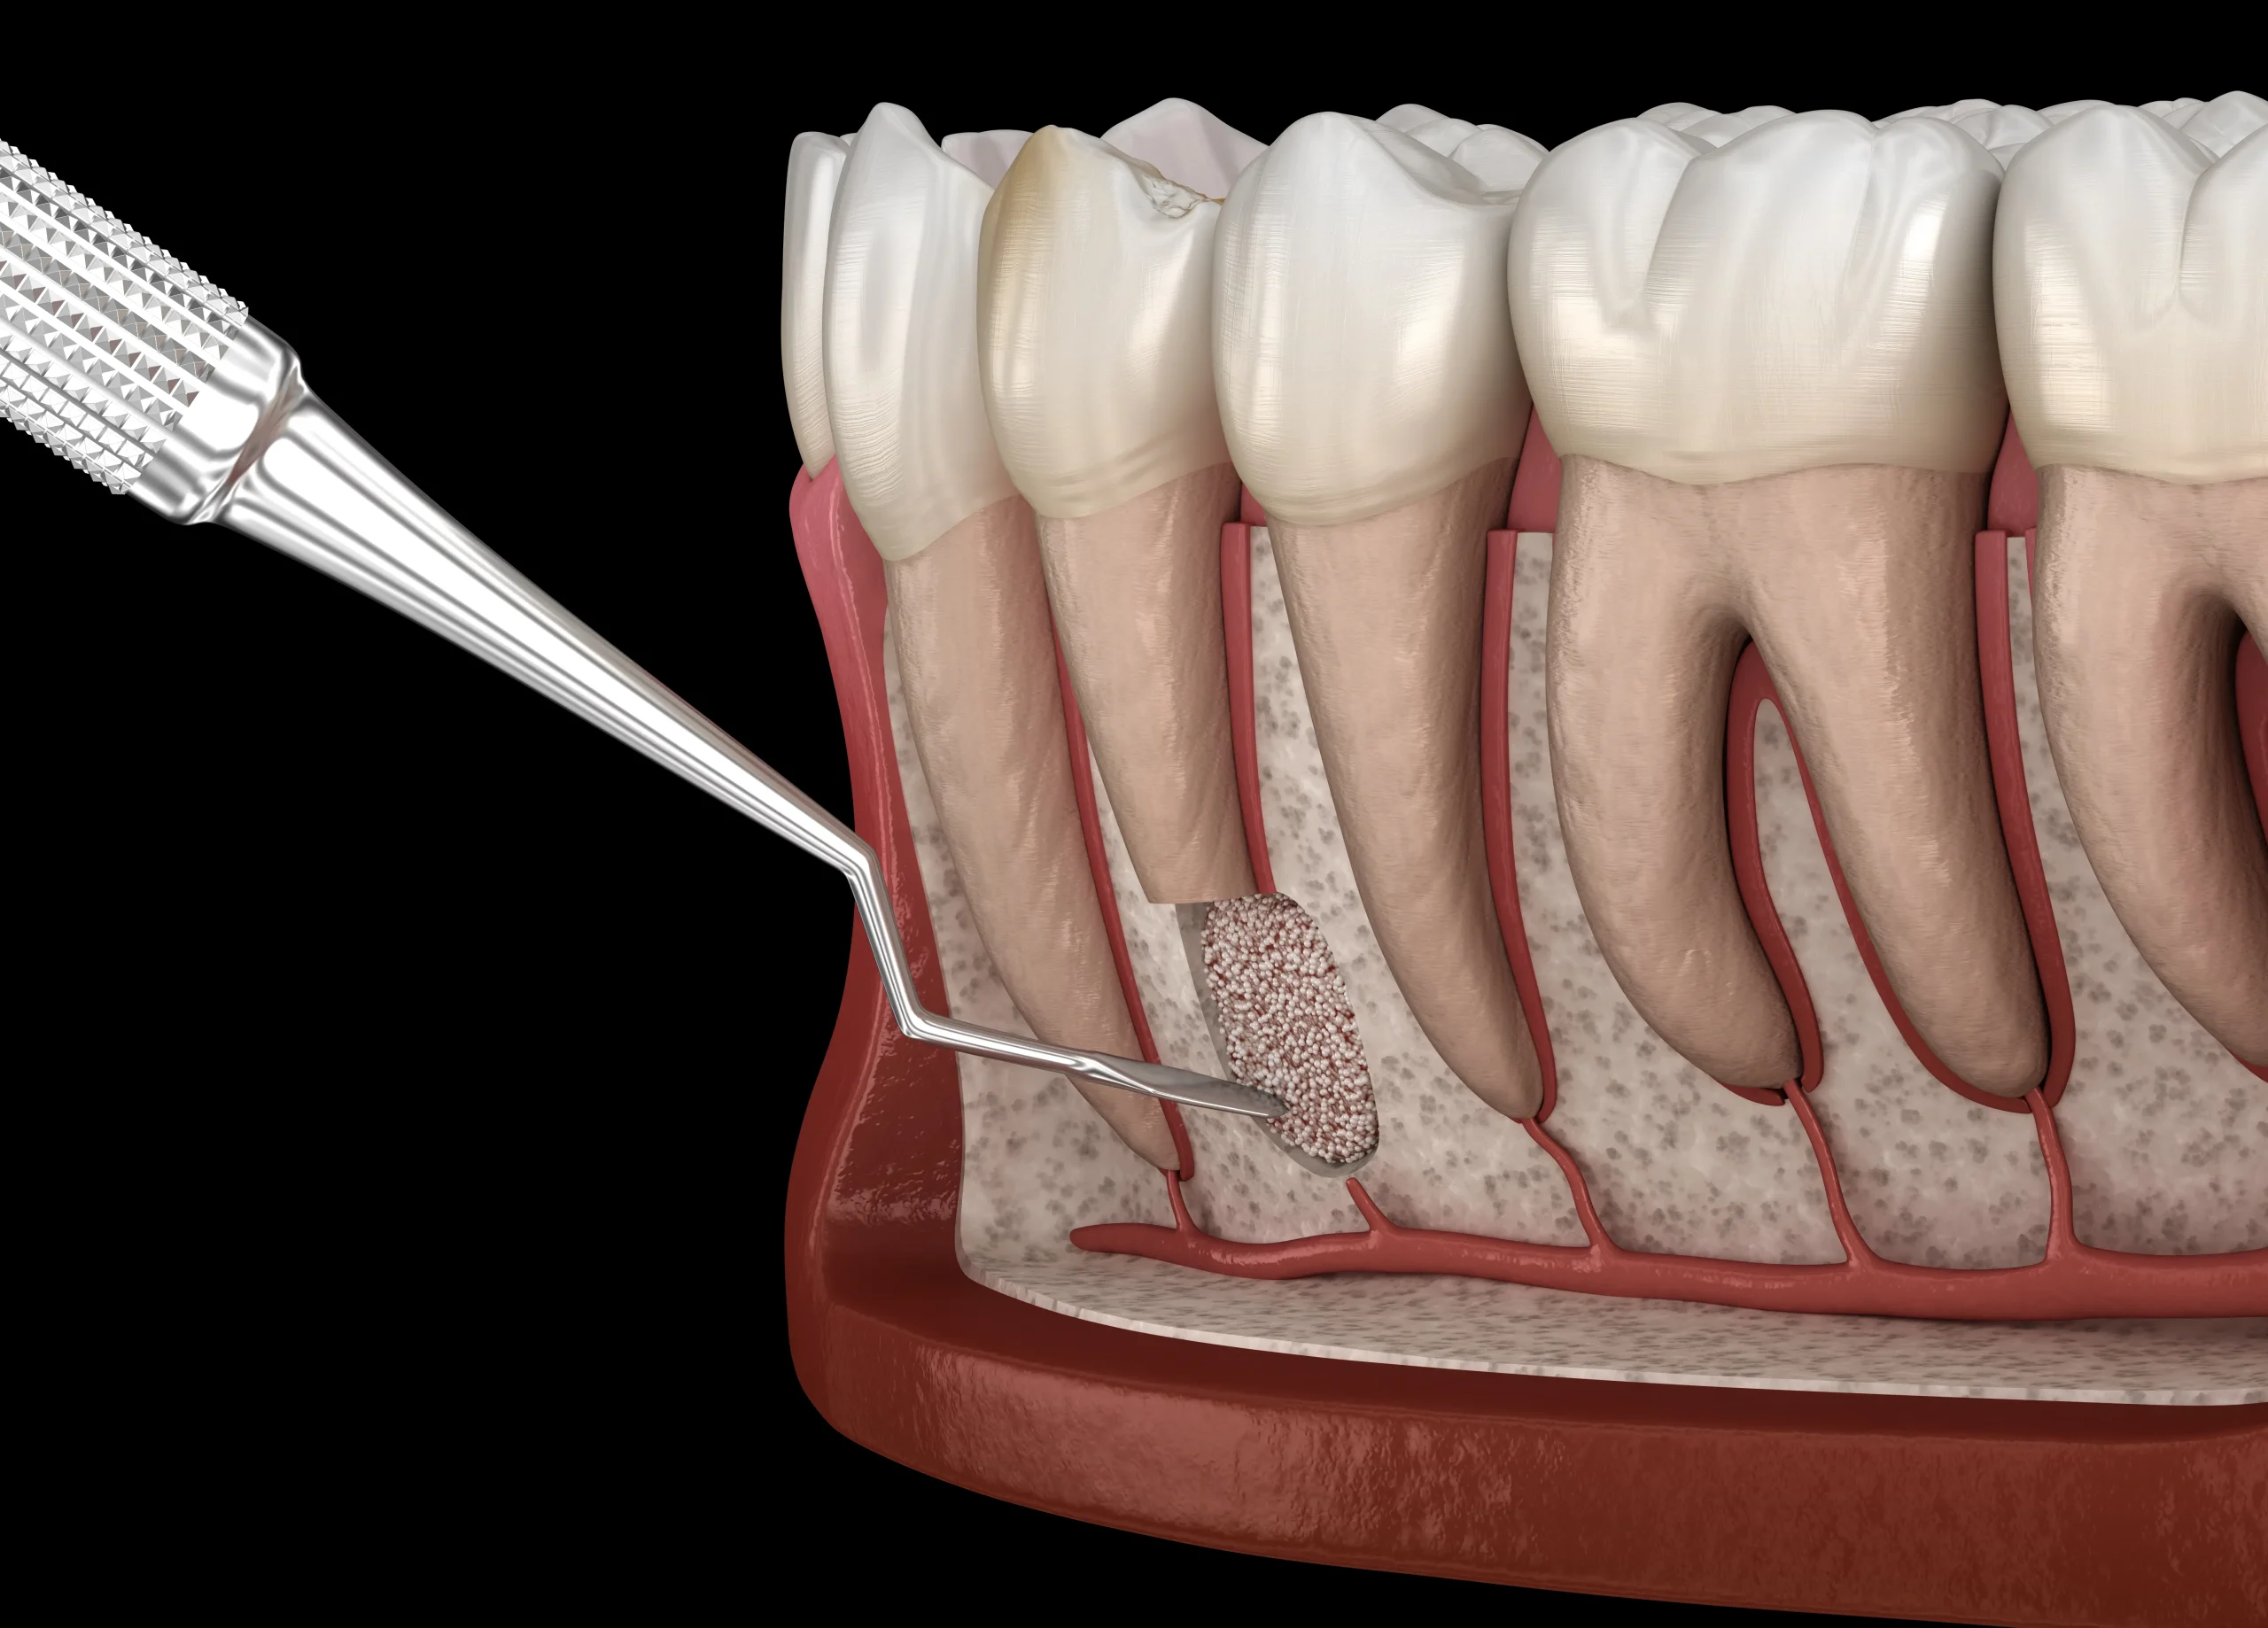

The canals are disinfected and shaped with rotary tools for accurate sealing and long-term success.

A biocompatible material is placed inside the canals to prevent reinfection and protect the tooth from within.